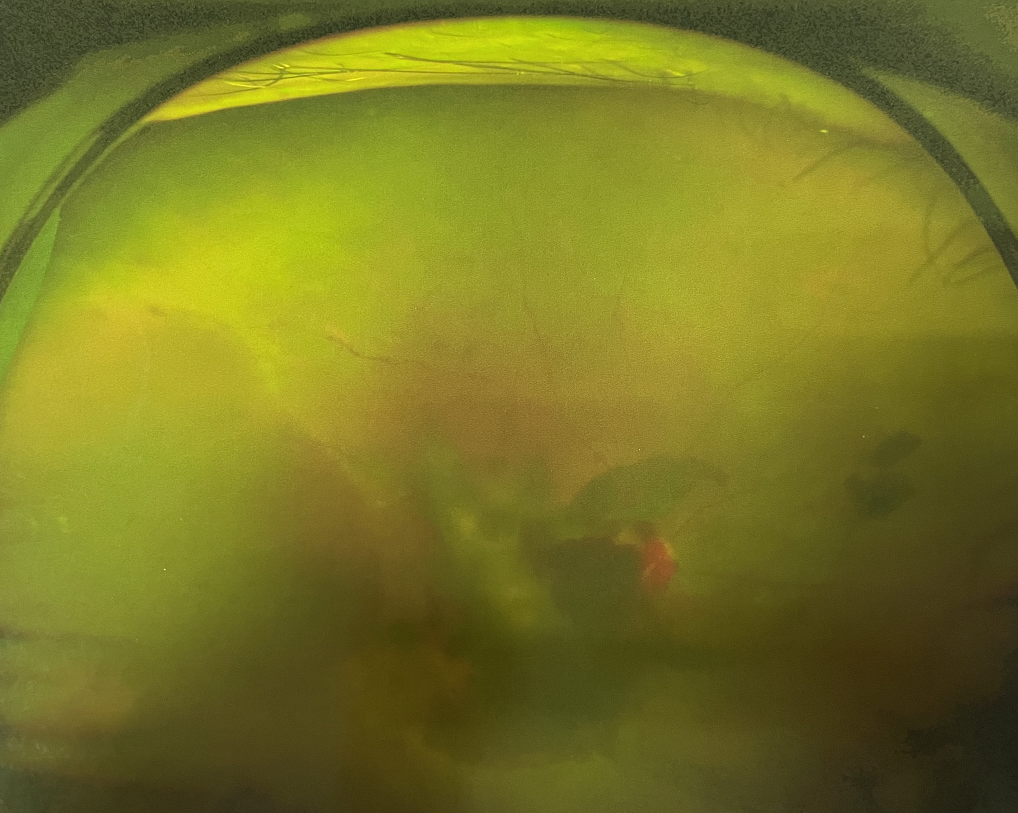

眼底病專科張小虎醫(yī)生檢查后,診斷王女士為“雙眼玻璃體積血、雙眼糖尿病視網(wǎng)膜病變V期”。(V期即5期,纖維增生期,出現(xiàn)纖維膜,可伴視網(wǎng)膜前出血或玻璃體出血。)

張小虎醫(yī)生為王女士進(jìn)行右眼玻璃體腔注藥術(shù),3天后進(jìn)行右眼23G玻璃體切割術(shù)后視力有所提升。

右眼術(shù)前